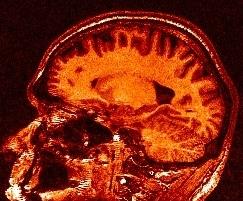

You may think that a unequivocal correspondence exists between the grey level in one voxel of a T1-weighted MR scan, and some esoteric property of the underlying cube of tissue. You should not succumb to this temptation. Take some time to observe a standard anatomical scan with a rainbow colormap to have this revelation:

Some parts of the white matter are red, while some others are yellow or even green. All looks like as if the putative correspondence mentioned above was depending on the localization in the field of view. Usually, the center of the coil is lighter, but this is not a systematic observation and depends on the coil and scanner design. When one looks at a MR slice with a grey colormap, like in standard radiology, this default is not straightforward. Human vision, indeed, is very effective at correcting for this kind of spatial variations. This capacity has some link with the fact that we usually perceive object's colors as uniform, whatever illumination related variations. Unfortunately, this sophisticated feature of human vision has prevented the MR physicists to find the motivation to overcome that acquisition problem. Artificial vision still being in its infancy, it is much more disturbed by these spatial intensity variations than radiologists. This procedure has to correct for the spatial bias before any segmentation process can be reliably trigered.